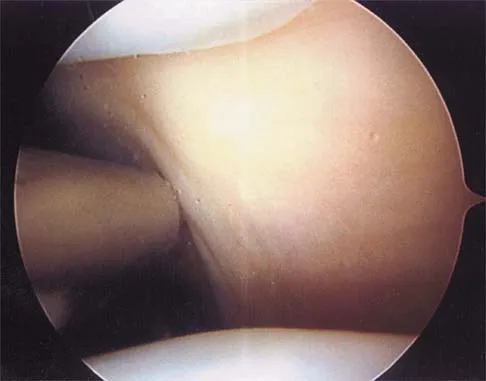

Figure 19 shows an arthroscopic view from the anterior lateral portal of the knee looking into the suprapatella pouch. The use of an electrothermal device during this procedure most commonly causes significant postoperative complications by damaging which of the following structures?

A 19-year-old soccer player feels a pop in his knee while making a cut and notes the development of an effusion over several hours. Examination reveals medial joint line tenderness, but the knee is stable to manual stress testing of all ligaments. Examination under anesthesia confirms a stable knee. What is the most critical factor in determining healing after repair of the lesion shown in Figure 14?